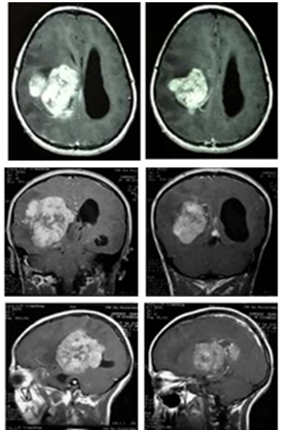

A 15years old girl, consulting for severe headache, with vomiting, and diplopia. The physical examination shows no motor or sensory deficit, and right 6th nerve pulsy, with papillary oedema grade 2. CT and MRI show a very large intraventricular tumor, located at the right lateral ventricle (Figure 3) (Figure 4). The patient underwent ventricular shunting, and the tumor was removed in a second time. The excision was total using a temporo parietal approach, and the post operative status was simple, with improvement of the headache. The histological exam indicates a fibroblastic meningioma too.

Figure 3 Axial, coronal and sagital T1-weighted +Gado MRIs showing a right lateral intraventricular meningioma.